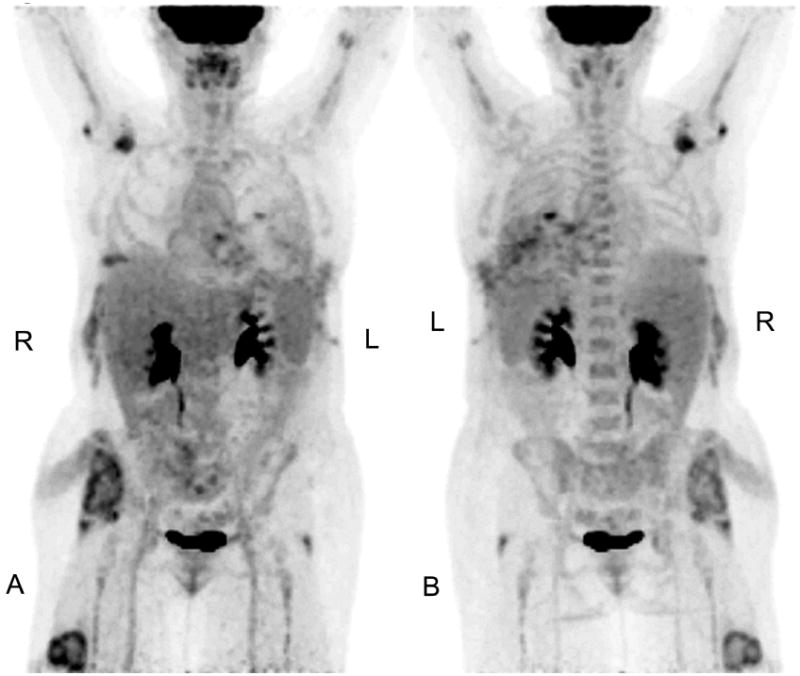

Figure 1.

Selected coronal views of maximum intensity projections (A=anterior, B=posterior) of attenuation-corrected maximum intensity projection PET images one hour after intravenous injection of 16.31 mCi of F-18 FDG are shown. The patient's blood glucose level was measured at 107 mg/dl before FDG administration. Several foci of atypical elevated glucose metabolism on the patient's right side are seen. Note radiotracer uptake in the left posterior ribs and soft tissue at the surgical entrance site.